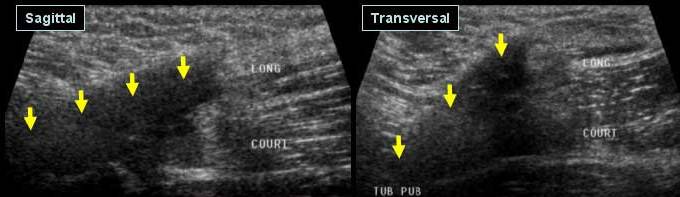

Antecedente de leziune a m. Ischio-gambieri cu persistenta unei jene la efort

Prezenta unei colectii fuziforme, bine delimitata, compresibila care va fi

Punctionata sub ghidaj ecografic